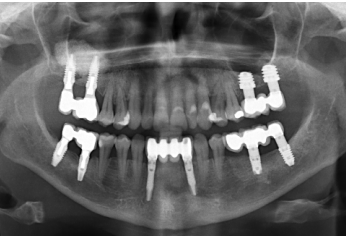

Finalmente, podemos observar la estabilidad de ambos tratamientos en la radiografía final a los 8 años, donde ambos se mantienen estables sin pérdidas óseas (Figura 13)